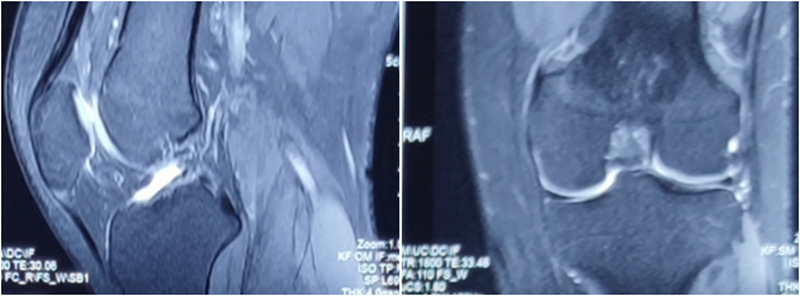

典型病例,张X,男,18岁,因扭伤致左膝关节疼痛伴活动受限1月余入院。

诊断:1.左膝前交叉韧带损伤;2.左膝外侧半月板损伤合并囊肿。

手术方案:左膝关节镜下清理、滑膜切除、外侧半月板部分切除成形、前交叉韧带重建术。

术前MRI